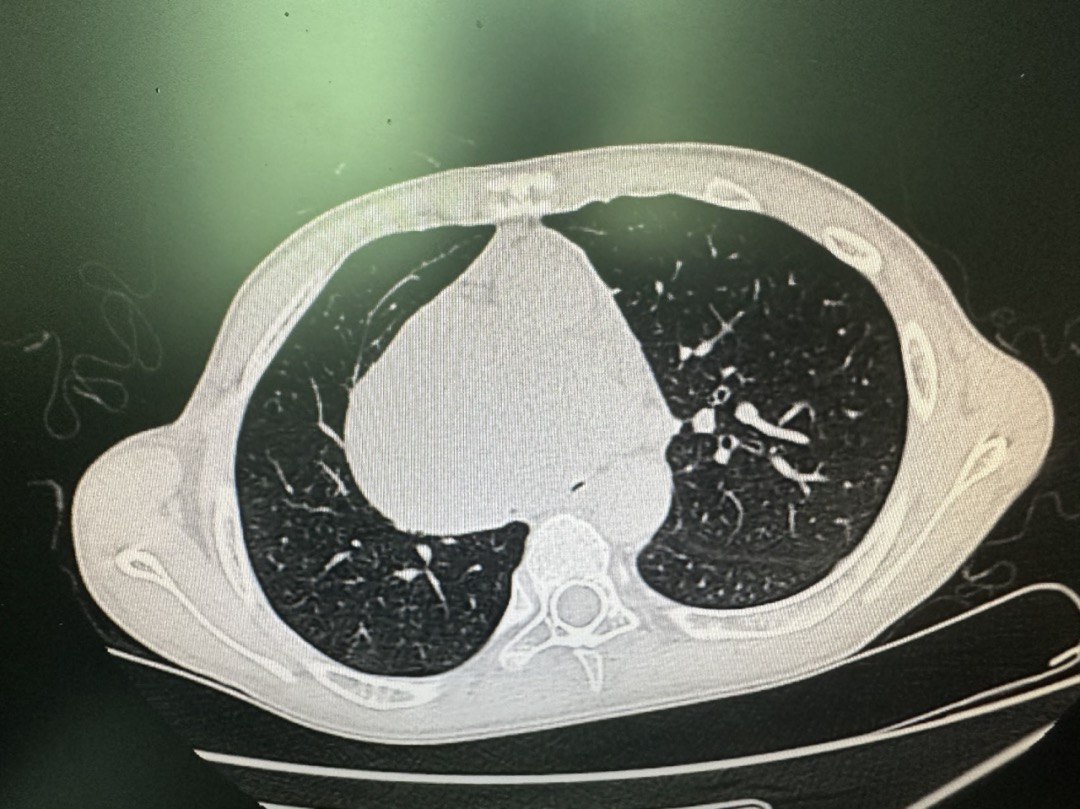

患儿麻醉风险不言而喻,随时可能发生窒息,为了防止使用肌松剂可能带来的肿瘤压迫风险,必须保留自主呼吸;但是即便顺利插入气管导管,尽可能多的越过气管受压部位到达隆突,也存在不能维持氧合的风险,因为患儿仅存左支气管不到10%口径的的管腔维持通气。

整个手术室气氛紧张压抑,麻醉科陈建颜主任面对压力迎难而上,带领麻醉团队开始有条不紊的进行麻醉诱导。陈宗副主任医师一边安抚患儿一边给患儿面罩吸氧,充分去氮,粟坤医生在患儿端坐位进行桡动脉穿刺测压,詹红飞医生在患儿端坐位进行股静脉穿刺置管,为ECMO备出生命通道。一切就绪下,陈主任指导分次给予麻醉药物,保留自主呼吸慢诱导半坐位成功插入ID6.0的气管导管,插管深度26cm,纤支镜下可见气管导管挤过气管受压部位,接近隆突上方。

劈开胸骨后,巨大的纵膈肿瘤暴露出来,在心胸外科肖海平主任精湛的技艺下,整个手术一气呵成,历时三小时,将肿瘤顺利切除!手术结束后,麻醉医师在纤支镜直视下,将气管导管插管深度退至20cm,送ICU继续治疗。在ICU茹晃耀主任团队精心照料下,术后第一天患儿就顺利转回普通病房,术后第三天拔除气管导管,目前患儿恢复良好!